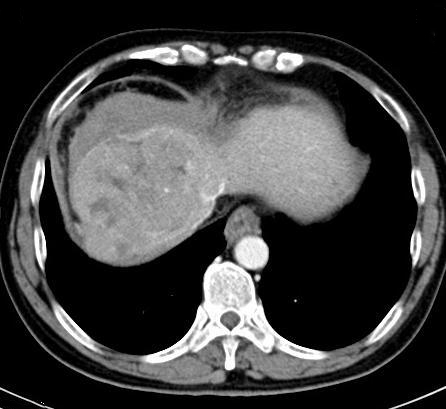

58岁的马先生(化名)凌晨突发腹痛来院就诊。CT 示患者肝右叶多发病变,B超示腹腔内大量积液,接诊医生考虑患者为肝癌伴破裂。此时患者已失血性休克。在开放四条静脉通路,连续快速补液2000-3000ml的情况下,患者血压仍只有90/60mmHg。患者被迅速送往手术室开展治疗。